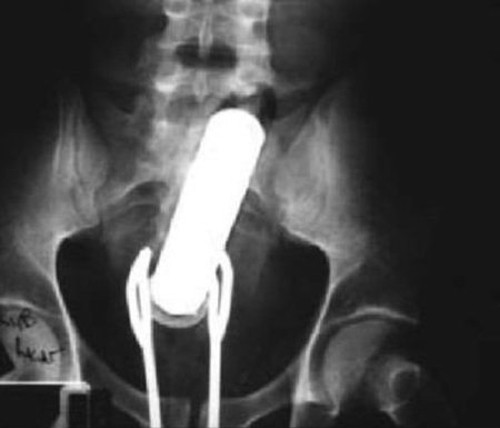

Trong lúc “tự sướng”, người đàn ông này vô tình để chiếc máy rung đi sâu vào cơ thể. Dù vậy thay vì đến các cơ sở y tế gần nhất để lấy dị vật, anh ta lại cố gắng tự lấy máy rung bằng một chiếc kẹp salad khiến nó cũng nằm lại trong đó.